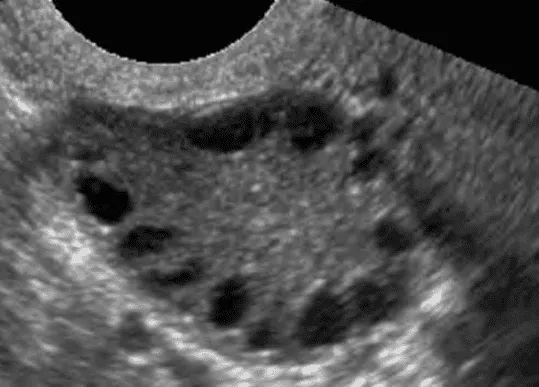

Hình ảnh “Chuỗi hạt kinh điển của buồng trứng đa nang. Các nang noãn nhỏ xếp thành chuỗi, phân bố ở ngoại vi buồng trứng”.

- Siêu âm có thể giúp định hướng nguyên nhân như u xơ tử cung, buồng trứng đa nang…